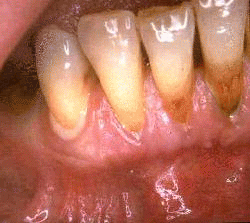

Periodontitis means inflammation of the supporting tissues of the teeth or also known as the periodontium. Periodontal disease can generally be divided into chronic, aggressive and necrotizing periodontal disease.

Chronic periodontitis can appear at any age but is most prevalent in adults. The disease is characterized by inflammation of the supporting structures of the teeth and loss of gum attachment due to destruction of the periodontal tissues. Prevalence and severity of the disease increase with age. The levels of chronic periodontitis can be classified as: Continue reading